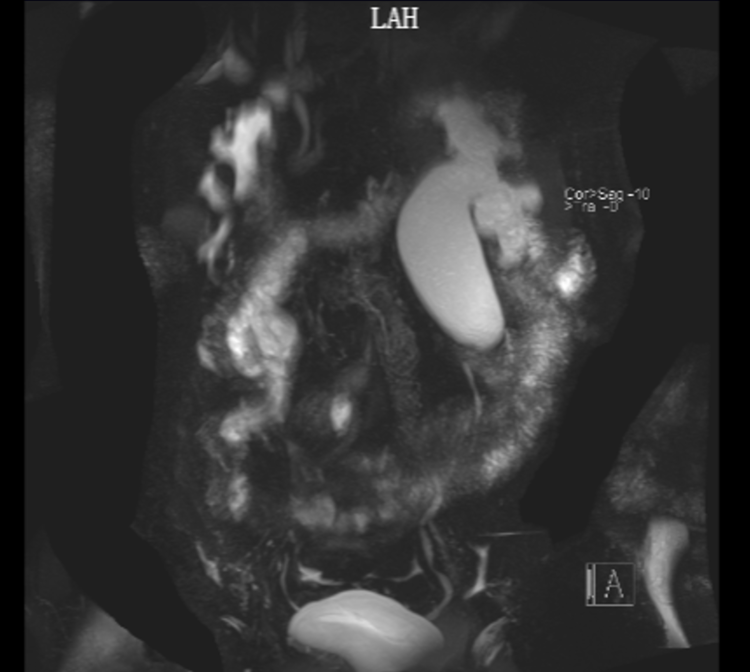

据了解,患者为45岁男性,既往20余年前因“双侧肾盂输尿管连接处狭窄”于市第二人民医院泌尿外科行双侧开放手术,术后均规律复查;1年前患者检查发现左肾积水、右肾萎缩,当时未特殊处理;2022年2月于外院查:肌酐514umol/l,予以左侧输尿管球囊扩张术,术后肌酐降至173umo/l;术后遵医嘱拔除输尿管支架。患者术后自觉反复恶心、纳差,来市第二人民医院经查:肌酐 315umol/l;MRI水成像显示:左侧肾盂输尿管连接处狭窄,右肾萎缩,肾功不全,手术指征明确;但患者有双侧开放手术史,再次行开放手术创伤大,且术后存在输尿管反复狭窄可能;长期留置并更换输尿管支架易反复感染且影响生活质量;经全科讨论并与患者及家属详细沟通后,行记忆金属支架植入手术。

术后患者恢复良好,次日复查肌酐 158umol/l,术后KUB(腹部平片检查)显示:Memokath新型热膨胀镍钛记忆合金输尿管支架,具有遇热膨胀、遇冷变软的物理特性;支架表面覆有特殊涂层,可以减少输尿管上皮细胞生长和结石的形成;且不适反应较小,能大大减轻患者痛苦、改善患者生活质量。